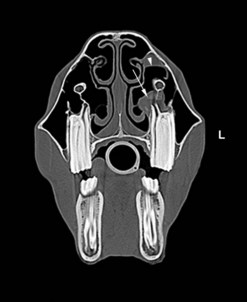

Dorsoventral projection (Figs 13.1213.13)

This view is quite easy to obtain in the sedated horse and is particularly useful for visualizing the ventral conchal sinus, nasal cavities, and nasal septum. Additionally, it can be used for evaluating maxillary/mandibular fractures; bony distortion of the maxilla associated with periapical infection of the rostral cheek teeth or intra-sinus masses. Laterally or medially displaced teeth and fractured maxillary teeth (particularly sagittal fractures) can also be visualized with this view; however, these abnormalities should be apparent during a thorough oral examination. The extremely dense bone of the hemimandibles makes it almost impossible to evaluate normally positioned mandibular cheek teeth using this projection.

An increased exposure is required for this projection compared to those used for lateral or lateral-oblique views of the skull. The X-ray beam is directed perpendicular to the dorsal plane of the head (which runs parallel to the hard palate) with the cassette held parallel with the ventral mandible and positioned as caudally as possible (Fig. 13.12). Because the mandibular cheek teeth rows are so close together (anisognathia), even a small degree of obliquity obscures one nasal cavity, ventral conchal sinus, and maxillary cheek teeth row and prevents accurate comparison of left and right maxillary sinus opacity; therefore, great care must be taken to ensure that the head is absolutely straight and the beam perpendicular to the dorsal plane. The centering point is in the midline of the dorsal aspect of the head at the level of the rostral aspect of the facial crests. Collimation of the primary beam should include the left and right lateral extents of the skull, the caudal aspects of the bony orbits and the diastemata, rostrally (Fig. 13.13).